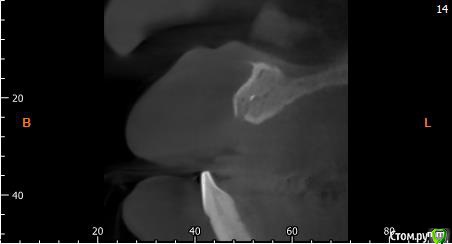

Собственно ситуация такая. Фронтальные зубы сверху были потеряны в результате серьезной травмы,  ! Фактически полное отсутствие костной ткани в области фронтальных зубов и по толщине и по высоте. Пациент ходит с чс протезом и хочет нечто несъемное.

Интересует как лучше это сделать при таких объемных дефектах.  Мои мысли первым этапом сосидж, потом 4 импланта. Но как быть с временным протезированием?

Тут нужна вертикальная аугментация с каркасной мембраной.